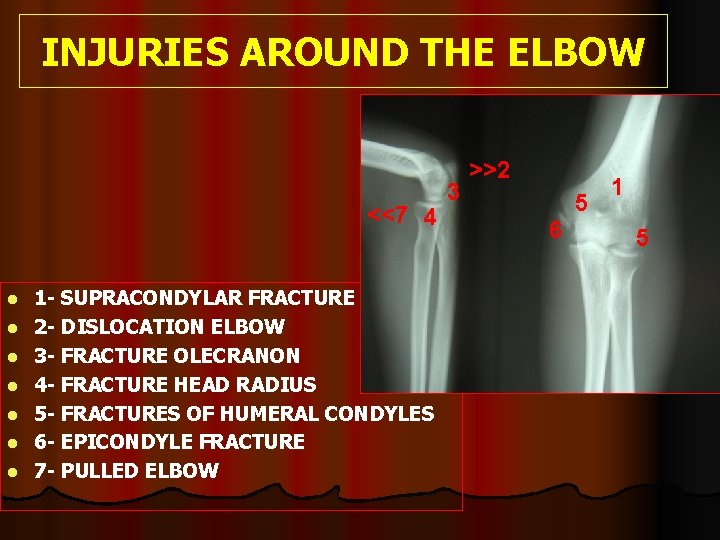

INJURIES AROUND THE ELBOW <<7 4 l l l l 1 - SUPRACONDYLAR FRACTURE 2 - DISLOCATION ELBOW 3 - FRACTURE OLECRANON 4 - FRACTURE HEAD RADIUS 5 - FRACTURES OF HUMERAL CONDYLES 6 - EPICONDYLE FRACTURE 7 - PULLED ELBOW 3 >>2 5 6 1 5